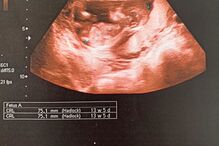

William Carvalho anunciou, através das redes sociais, que vai ser pai pela primeira vez e que o pequeno Bryan "nascerá em breve". Na publicação, em que mostrava a ecografia do bebé, não fez qualquer referência à mãe da criança, com o caso a estar envolto em secretismo.